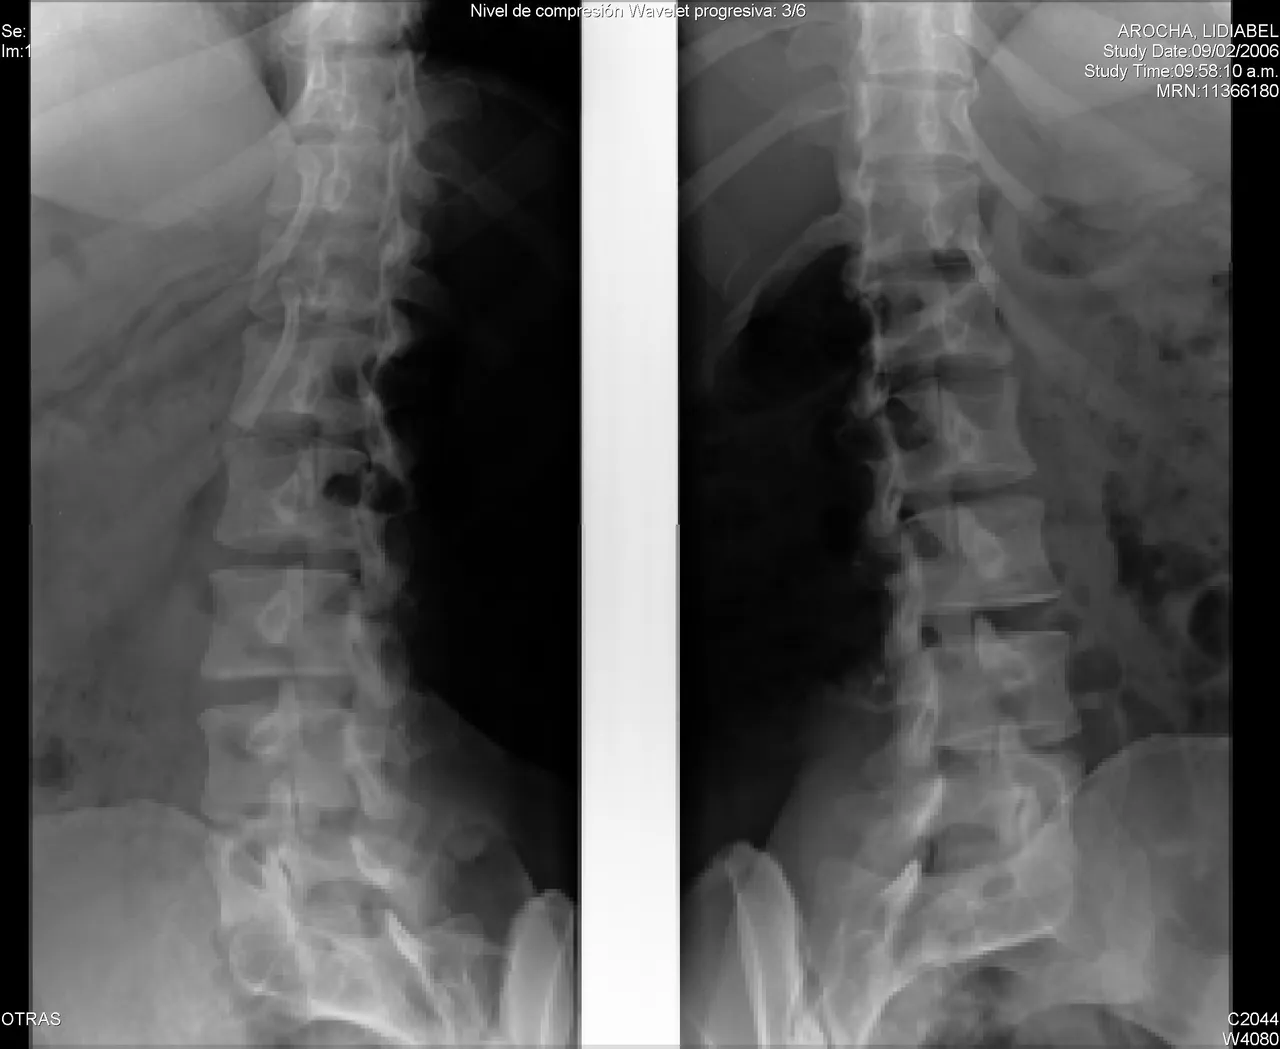

A spinal fracture (spinal compression fracture) occurs when one of the bones in the spine fractures or collapses.

These fractures occur most often in the fifth vertebra of the spine or lumbar spine, although they can also occur in the fourth lumbar vertebra. Fractures may occur on one or both sides of the pars bones. In more severe cases, spondylolisthesis may develop. This occurs when a fractured pars bone separates, allowing the injured vertebra to move forward.

Report any new or unusual back pain to your doctor right away. Early diagnosis can lead to more treatment options. A physical exam, along with an x-ray, can help determine whether or not you have a spinal fracture.